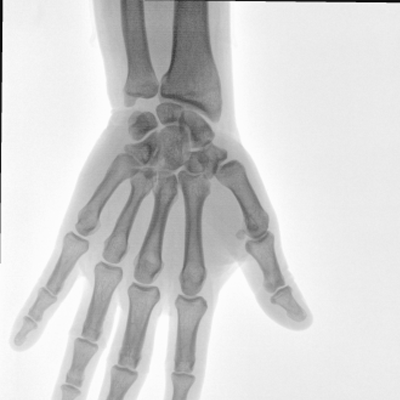

臨床適用科室:骨科、普通外科、矯形外科、創傷外科、泌尿外科、脊柱外科、疼痛外科、消化科、婦科等科室。

大尺寸動態平板探測器,高DQE、低噪聲、圖像清晰。采用多分辨率圖像增強處理技術,不同部位不同圖像處理算法,滿足客戶多樣化的需求。